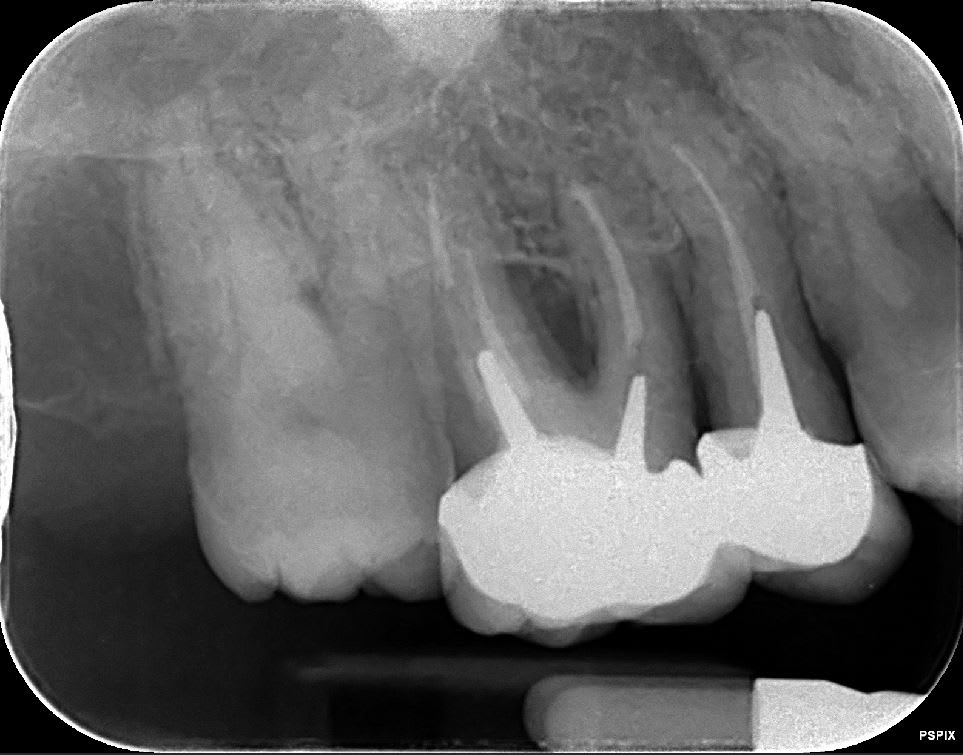

la retro c'est aussi de chez acteon, le pspix2, les erlm sont de chez eux. Que reprochez vous ? Image trop flou ? Vraiment bcp plus flou que chez un concurrent ? Pensez vous que cela vienne des capteurs ou de la machine avec un mauvais reglage de netteté, ou un mauvais réglage tension, intensité,temps exposition ?

11 21 et 15 16 sont solidarisées ??

Pour les rétro je trouve qu'elles sont pas nettes... moins nettes que la pano.

Peut être que c'est le filtre quand tu exportes les clichés.